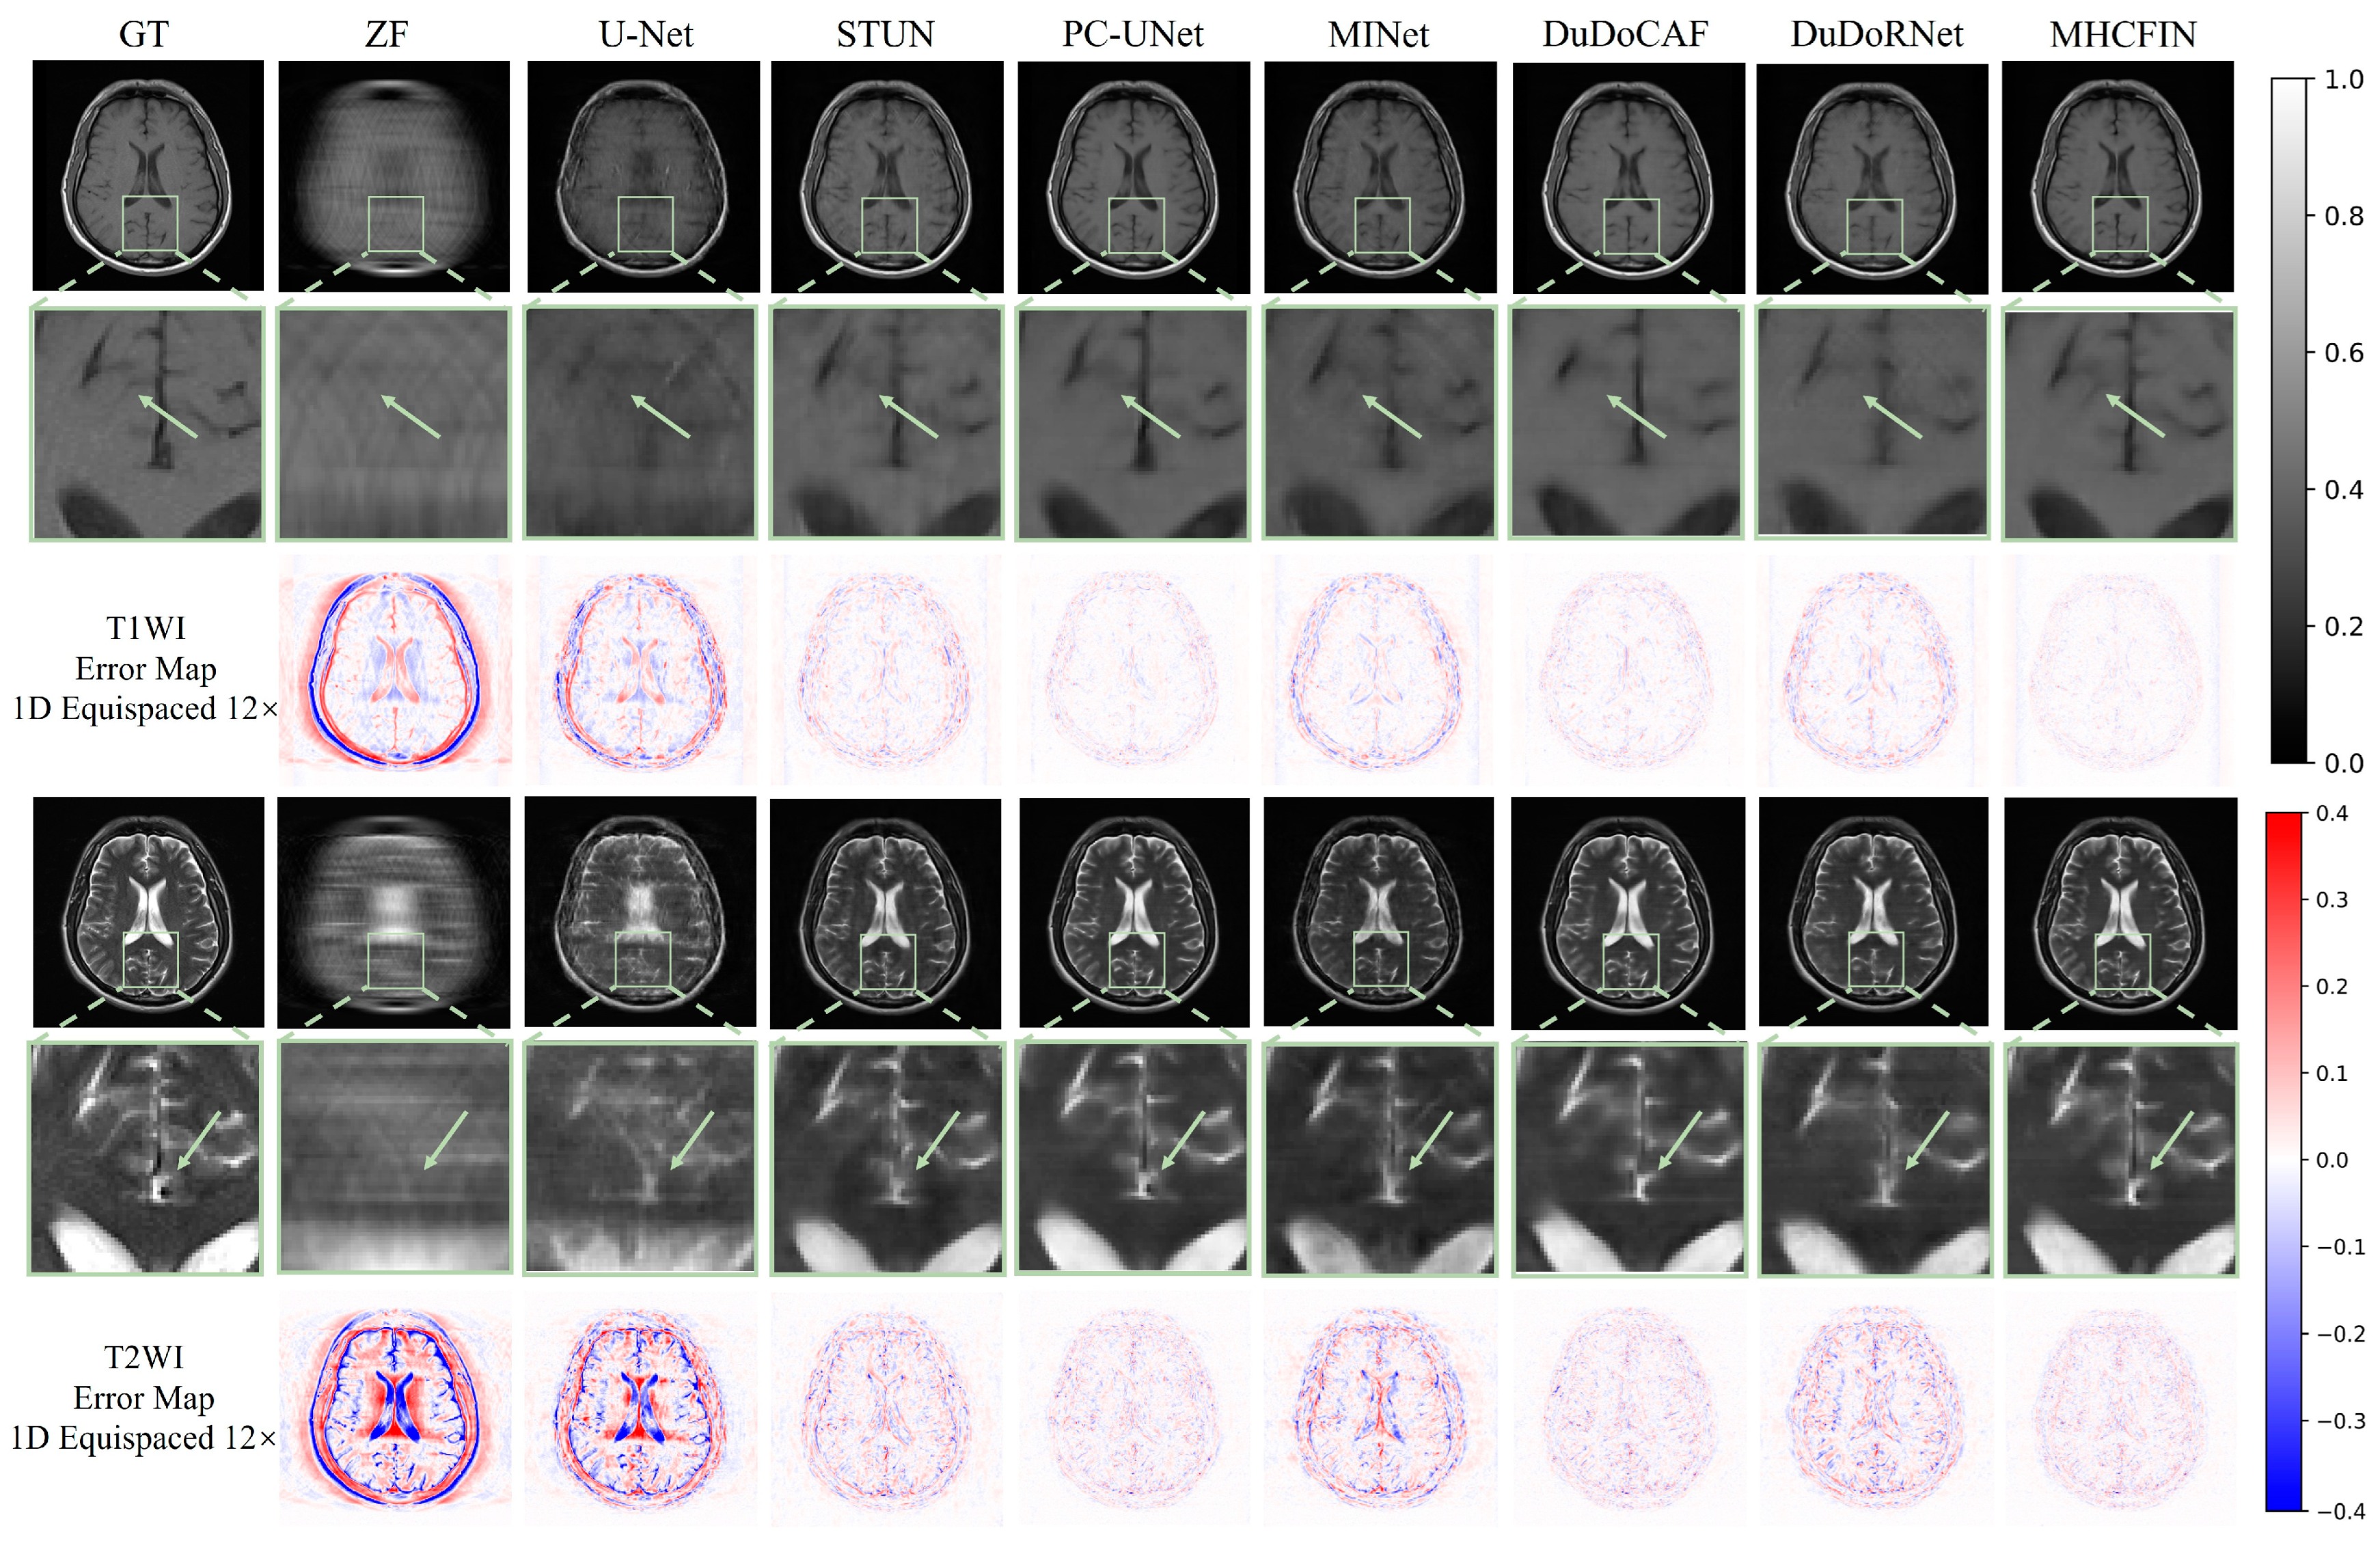

5.2. Qualitative Results